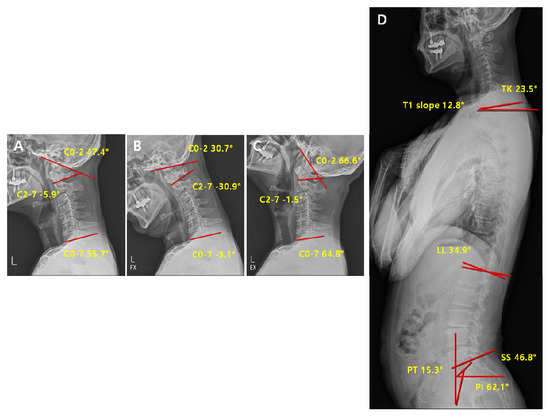

| Parameters | Definition |

|---|---|

| C2-7 Cobb angle | The intersection angle between the line perpendicular to the line parallel to the C2 lower endplate and the line perpendicular to the line parallel to the C7 lower endplate |

| C0-2 Cobb angle | The occipito-cervical angle, which is the intersection angle between the McGregor line and the line parallel to the C2 lower endplate and is used to evaluate the curvature of the upper cervical spine |

| C0-7 Cobb angle | The intersection angle between the McGregor line and the line parallel to the C7 lower endplate |

| C0-2/C0-7 | The value of C0-2 Cobb angle divided by C0-7 Cobb angle |

| C2-7/C0-7 | The value of C2-7 Cobb angle divided by C0-7 Cobb angle |

| T1 slope | The intersection angle between the tangent line and the upper plate of the T1 vertebral body |

| SS (Sacral Slope) | The angle formed by a line drawn along the endplate of the sacrum and a horizontal reference line |

| PT (Pelvic Tilt) | The angle formed by a line drawn from the midpoint of the sacral endplate to the center of the bicoxofemoral axis and a vertical and a vertical plumb line |

| PI (Pelvic incidence) | The angle formed by two vectors: (1) The line joining the bicoxo-femoral axis to the center of the sacral end plate and (2) A line perpendicular to the sacral endplate |